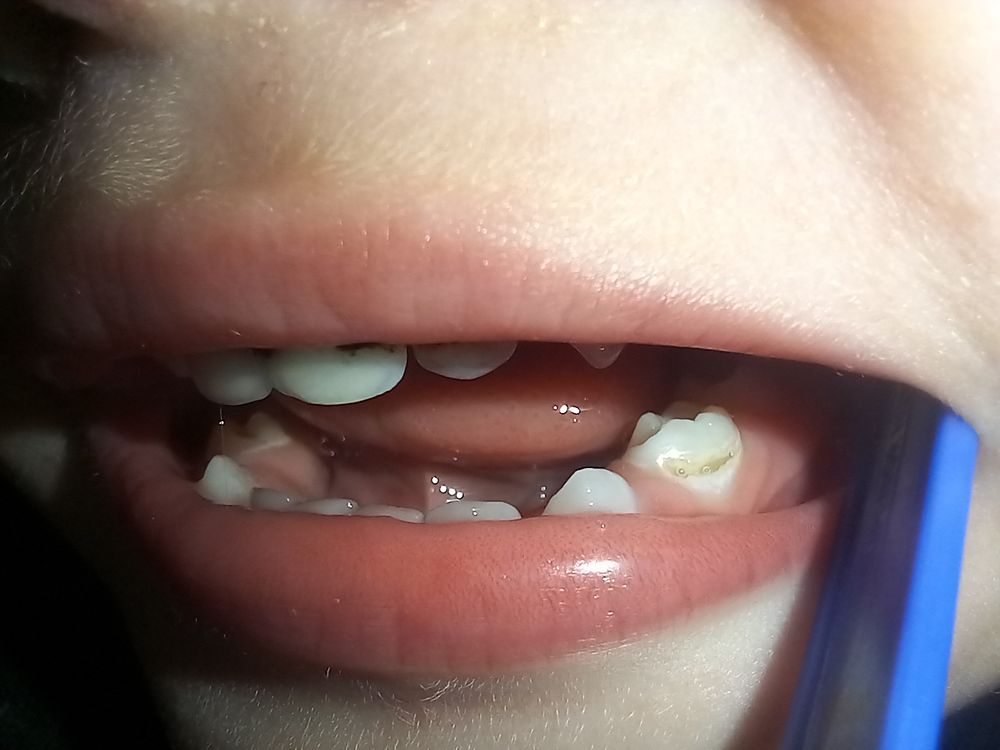

Юлия, вот купил щетку колгейт 2+ заяц. За 2 недели утром и вечером смог убрать налет с зуба и обнажилась полость с боку 4го зуба нижнего с обоих сторон челюсти у этих зубов. Что же делать ....